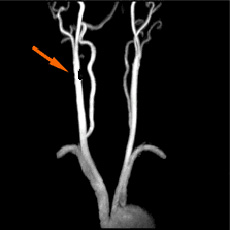

頚部MRA

• 頸部MRA正常

正常(狭窄を認めず)

• 頸部MRA右内頸動脈50%狭窄

右内頸動脈50%狭窄

• 頸部MRA2mm大の脳動脈瘤

2mm大の脳動脈瘤

• 頸部MRA20mm大の巨大脳動脈瘤

20mm大の巨大脳動脈瘤